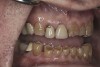

(6.) Preoperative right lateral, open view.

Figure 6

(7.) Preoperative anterior, open view. Note the significant amount of wear, erosion, and abfraction lesions.

Figure 7

(9.) Preoperative right lateral, closed view.

Figure 9

(10.) Preoperative anterior, closed view. Note the end-to-end occlusion of the anterior teeth and the wear on the incisors and centrals resulting in no anterior or canine guidance.

Figure 10

(11.) Preoperative left lateral, closed view.

Figure 11

(12.) Preoperative right anterior, close-up view.

Figure 12

(13.) Preoperative anterior, close-up view.

Figure 13

(14.) Preoperative left anterior, close-up view.

Figure 14